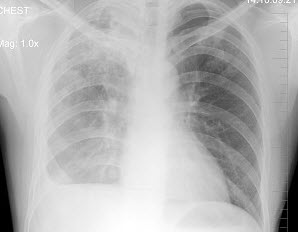

261、多项选择题

男,1岁零8个月,生长发育差,易患呼吸道感染,心悸气促,心脏正、侧位片检查如图所示,正确的描述和诊断是()

A.正位示心影向两侧扩大,心尖左移

B.肺纹理增多

C.侧位示心前间隙变窄,心后食管前三角间隙消失

D.房间隔缺损

E.室间隔缺损

点击查看答案